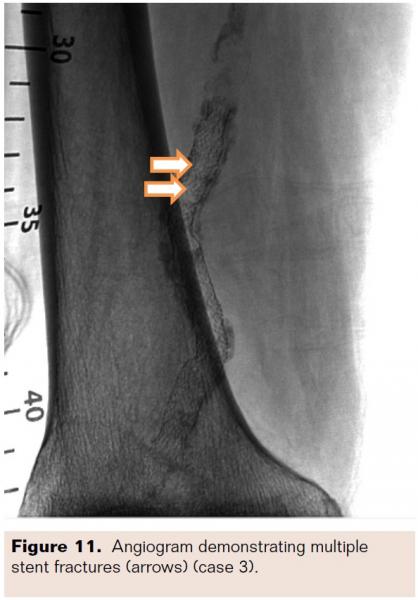

Following the 8 passes (Figure 5), the TT was removed and the angioplasty balloon was inserted to the lesion site. One inflation with the balloon at 18 atm for 120 seconds reduced the diameter stenosis to 24% (Figure 6). Long, slow inflations are recommended to prevent vessel dissections and tissue recoil. The procedure was successful with no adverse device-related events. This patient was followed for 12 months without the need for revascularization.